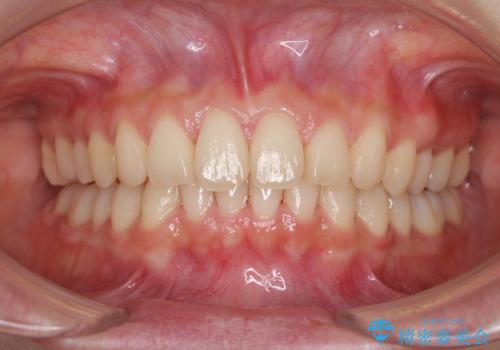

インビザラインによるディープバイトの改善

- 口元の前突感と深い咬み合わせ(ディープバイト)を気にして来院された患者様です。

インビザラインによる上下歯列の遠心移動(後方移動)と、それに伴う近心傾斜(前方傾斜)の改善により、口元の突出感とディープバイトを改善することとしました。

前歯のデコボコを最も気にしていましたが、咬み合わせが深く歯ぎしりが自由にできない点を指摘すると、常に食いしばってしまうことも悩みであることが分かりました。

咬合状態が大きく変化したため、治療後半では咬み合わせの位置が定まらなくなりました。上下の前歯に後戻り防止用のワイヤーを装着し、奥歯の咬合をフリーにしたことで1ヶ月ほどで咬み合わせが定まりました。